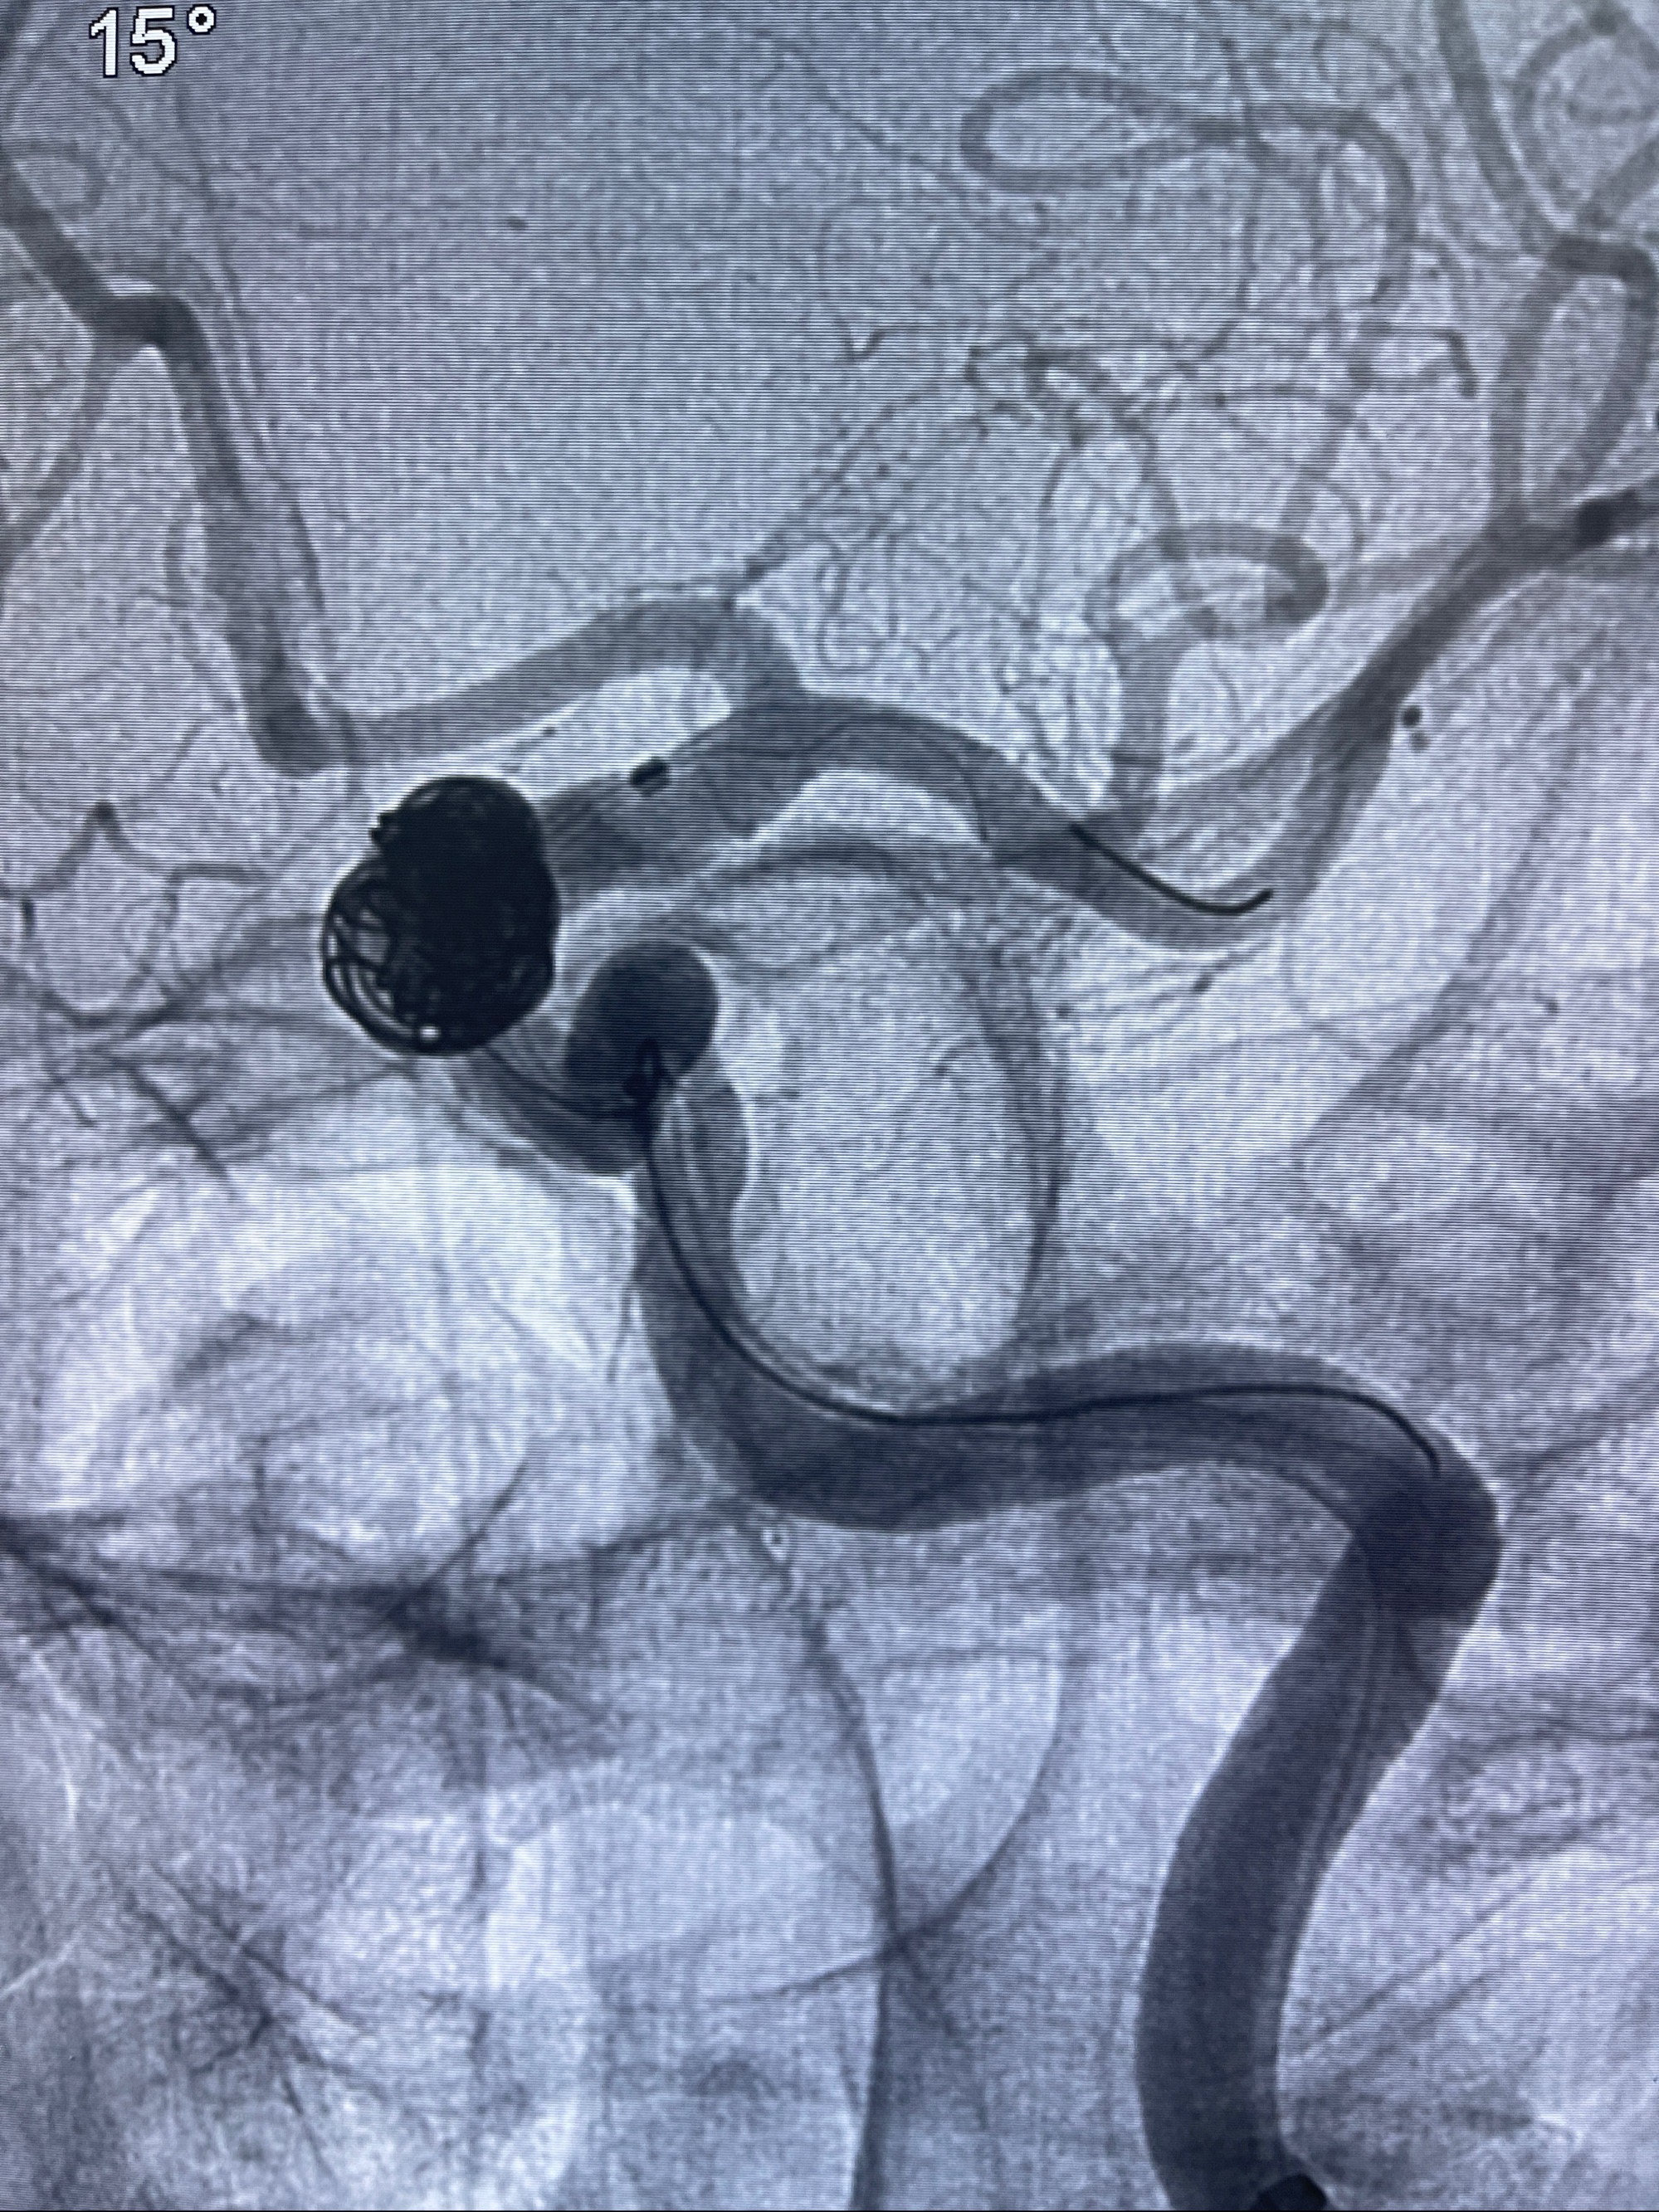

2023-08-30DSA:左侧颈内动脉眼动脉动脉瘤,约3*9.2*7.3mm大小

2023-09-06全麻下行左侧颈眼动脉瘤

密网支架辅助栓塞

- Tubridge 4.0-20mm密网支架

- 加奇微弹簧圈:7*30/6*20/5*20/2*8

术后3D显示支架贴壁佳